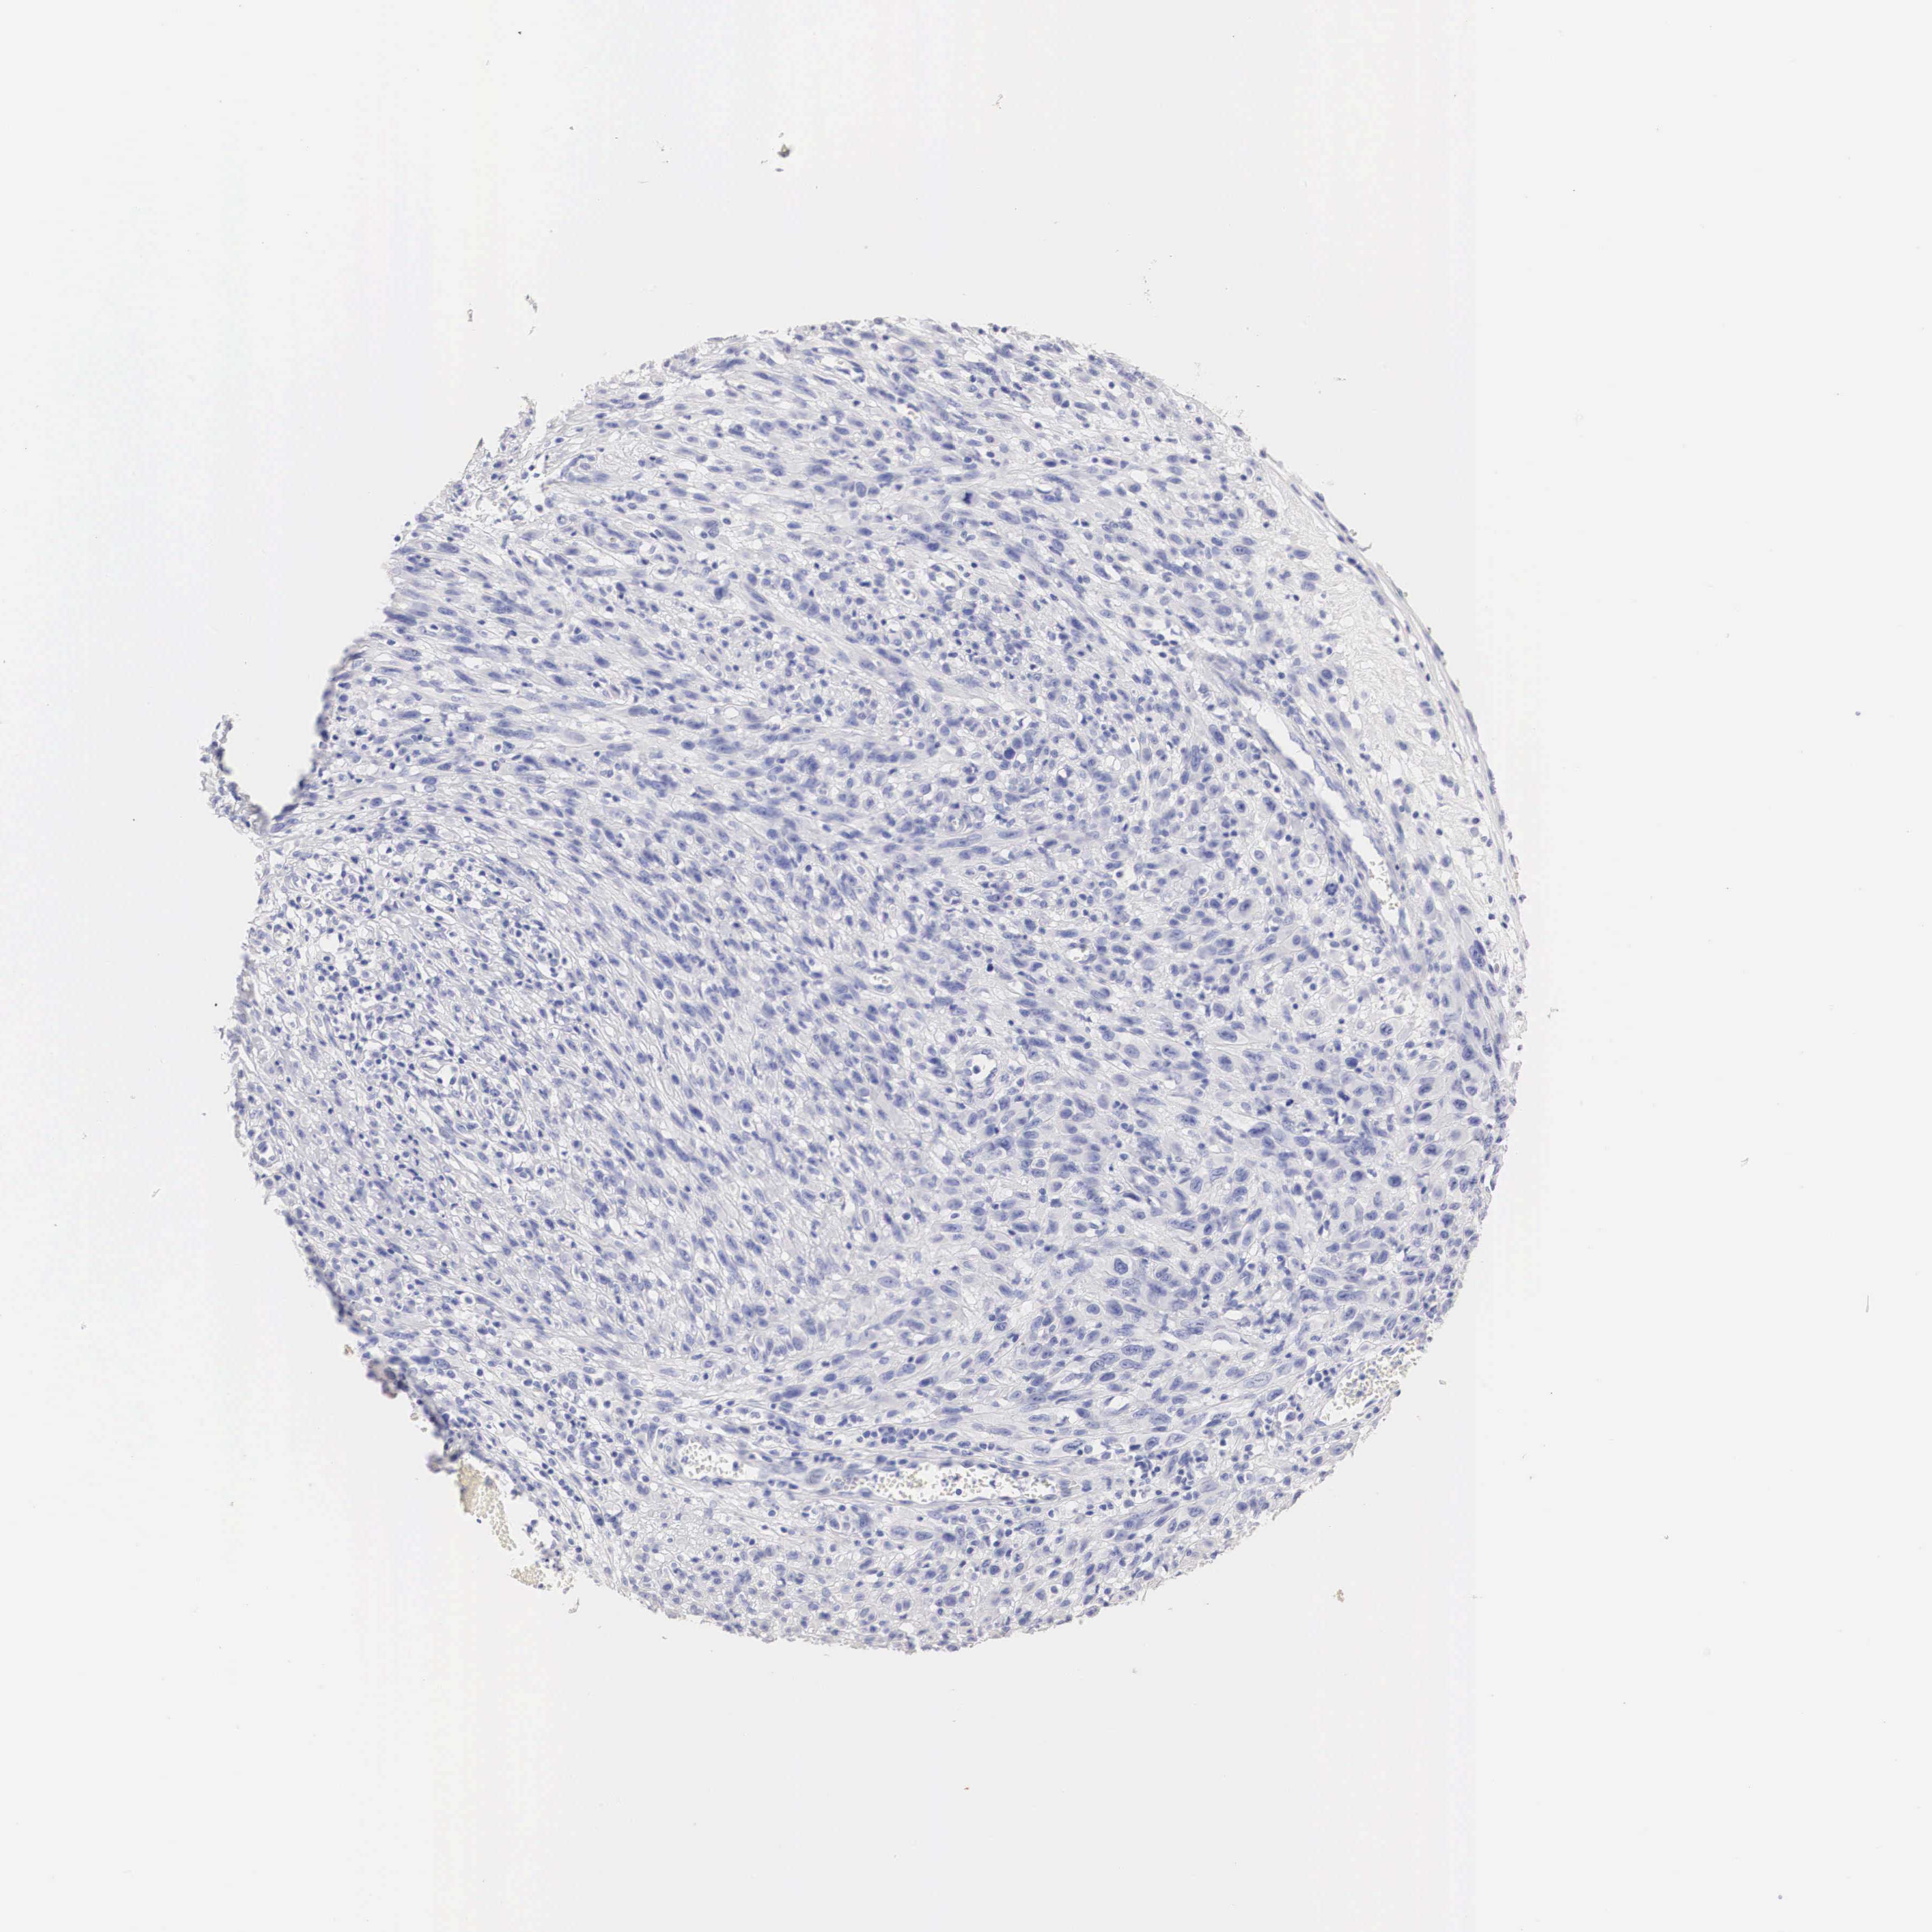

MELANOMA - Protein expressioni

A mouse-over function shows sample information and annotation data. Click on an image to view it in a full screen mode. Samples can be filtered based on level of antibody staining by selecting one or several of the following categories: high, medium, low and not detected. The assay and annotation is described here.

Note that samples used for immunohistochemistry by the Human Protein Atlas do not correspond to samples in the TCGA dataset.

Antibody stainingi

Antibody staining in the annotated cell types in the current human tissue is reported as not detected, low, medium, or high, based on conventional immunohistochemistry profiling in selected tissues. This score is based on the combination of the staining intensity and fraction of stained cells.

Each image is clickable and will lead to virtual microscopy that enables deeper exploration of all samples and also displays staining intensity scores, fraction scores and subcellular localization as well as patient and tissue information for each sample.

Antibody HPA001383

Antibody CAB000043

Antibody CAB020416

Antibody CAB062555

Staining

High

Medium

Low

Not detected

Intensity

Strong

Moderate

Weak

Negative

Quantity

>75%

75%-25%

<25%

None

Location

Nuclear

Cytoplasmic/membranous

Cytoplasmic/membranous,nuclear

Malignant melanoma, NOS

Malignant melanoma, Metastatic site